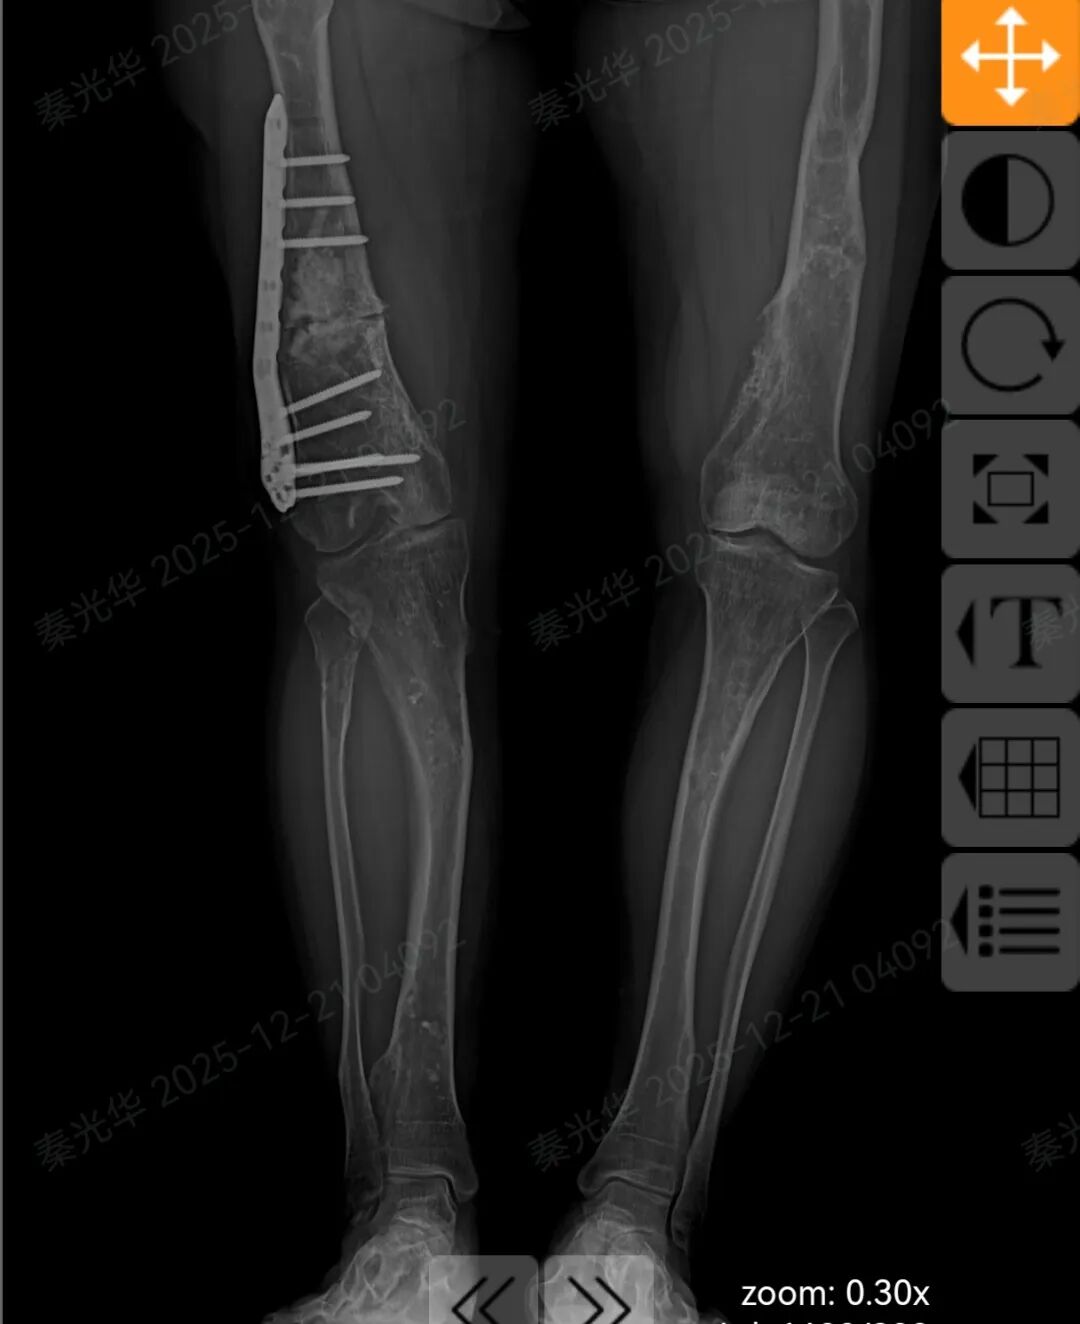

术后患者右侧股骨形态恢复正常,双下肢成功等长!

患者术后核磁显示双下肢恢复等长